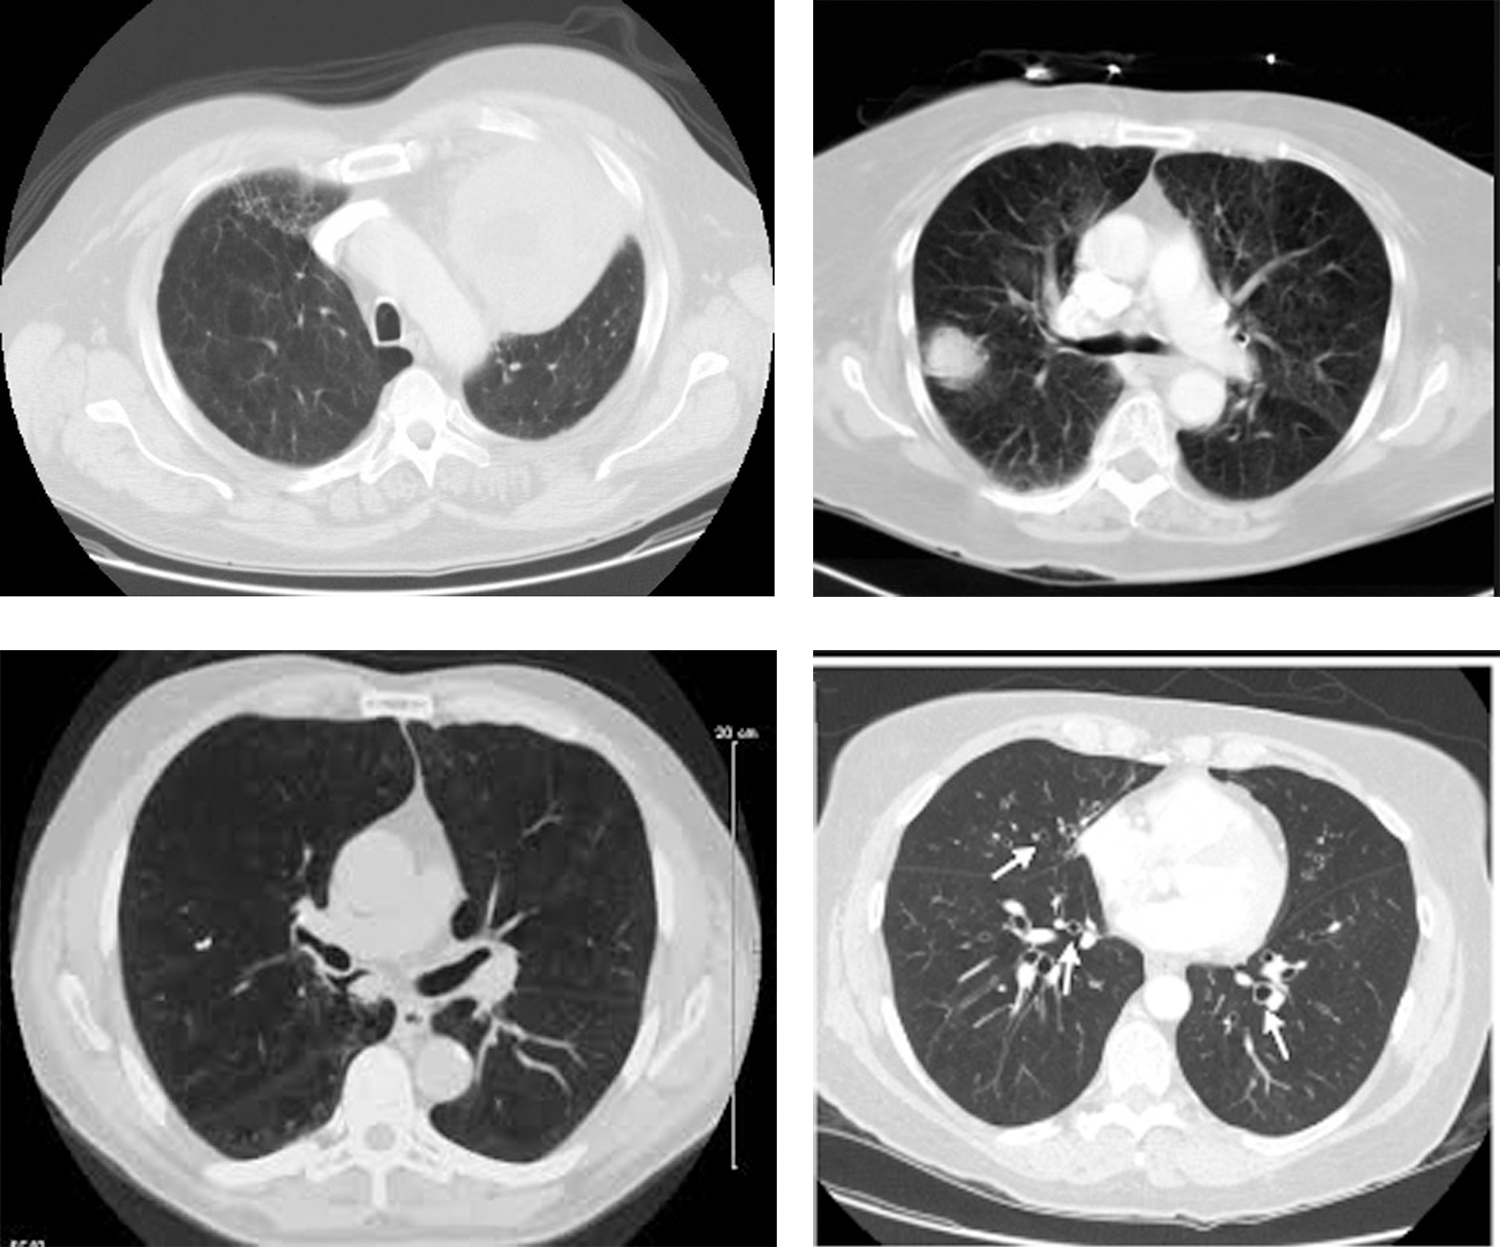

The repository has provided expert opinions about the images. Some of the sample images are shown in Fig. 5.

Figure 5: Sample CT images of lung cancer